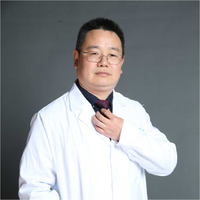

先看2024年6月的影像:

靠叶裂侧密度高、实性,灶内空腔多房,有微小血管走向并进入病灶的囊壁内,叶间裂有受牵拉。

囊壁明显厚薄不均,内壁也不光滑,而整体轮廓与边界却较为清楚。

部分边缘有细毛刺样征、中间密度低些,边上有囊腔,有的地方有少许磨玻璃成分,见到有小血管多处进入病灶。